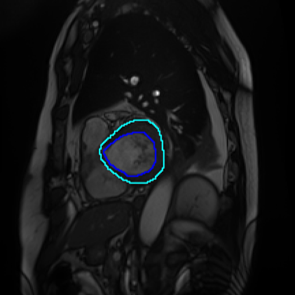

Figure 1: Different sections of a heart. (a) represents the basal section, which lacks regions of the right ventricle(RV), myocardium, and the left ventricle(LV); (b), (c), and (d) approach the apical section, while the RV, myocardium, and LV vary in size and shape.

French et al.[13] emphasized that consistency regularisation requires robust and diverse perturbations in semantic segmentation, which leads networks to possess a strong ability to generalize. Perturbations are usually performed using a set of data augmentation algorithms, and consistency regularization uses highly augmented images to efficiently learn unlabelled data. In terms of the intricate anatomical shapes in greyscale medical images, data augmentation algorithms should be able to enable the segmentation model to identify the shapes of objects, especially contours. Furthermore, medical images sometimes do not contain objects from some specific classes, which can lead to inter-class imbalance (Figure 1). To address these challenges, we introduce Scaling-up Mix with Multi-Class (SM22{}^{2}start_FLOATSUPERSCRIPT 2 end_FLOATSUPERSCRIPTC), a novel data augmentation algorithm based on image mixing techniques to generate a more diversified training dataset. Targeting the primary tasks of semantic segmentation - region and contour recognition - our algorithm processes the shapes of segmentation objects and merges semantic features from multiple original images into a novel composition. We incorporate the method into a pseudo-labeling framework to improve the teacher model’s ability to learn unlabeled data and conduct experiments on three medical image datasets.